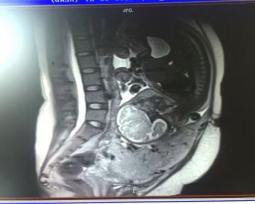

动脉球囊阻断术辅助前置胎盘手术临床应用(2019年9月开始我院第一例手术)

治疗效果确切疾病:中央性前置胎盘、胎盘植入